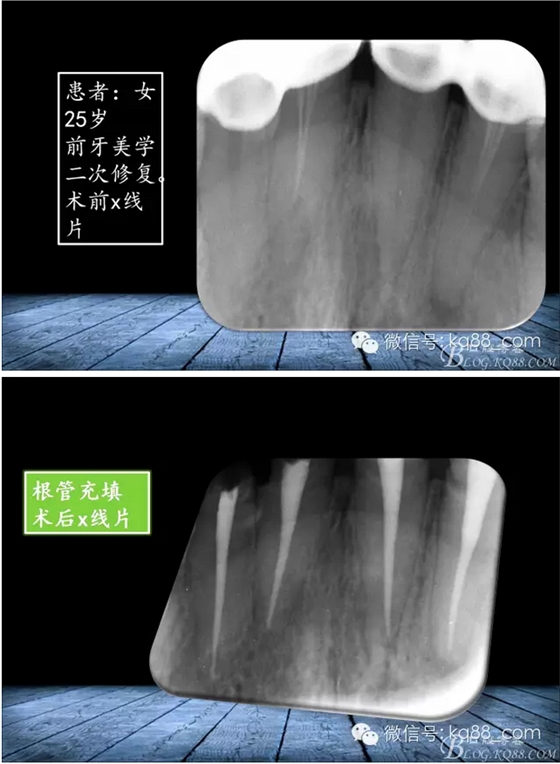

QQ圖片20150817140811.png

QQ圖片20150817140835.png